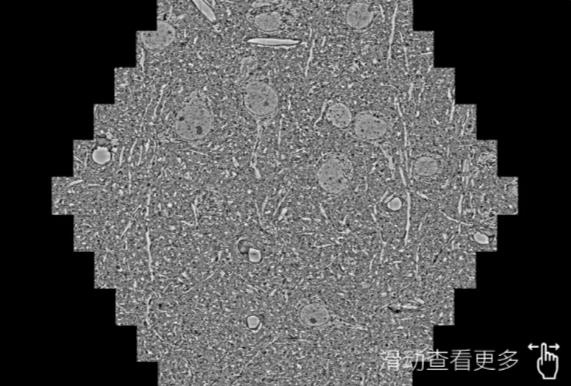

鼠脑切片。左图使用忠县蔡司忠县扫描电镜MultiSEM706对165μmx143pm面积区域成像,耗时仅需1.5秒。右图为鼠脑切片中30μm区域放大效果。样品由芝加哥大学B.Kasthuri提供。

使用蔡司高速忠县扫描电镜MultiSEM对1mm²人脑皮层组织进行高分辨成像,并对其中的各种细胞结构进行三维重构分析。左图展示了2x3mm²组织平面中锥体神经元的三维重构效果。右图显示了局部体积神经元三维重构。图像由哈佛大学chtman实验室提供,渲染图由D. Berger 制作。